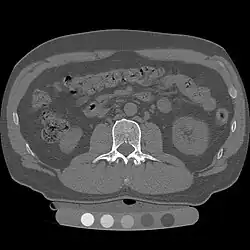

Thoracic and Lumbar Spine Clearance

Unfortunately, the NEXUS and Canadian C-Spine rules do not apply to suspected thoracic or lumbar injury; indeed, there are currently no validated guidelines for who requires imaging in this setting.[4][6] Instead, imaging should be obtained according to physician gestalt.[6] High-risk features include tenderness in the center spine, new numbness or weakness, or spinal fracture of another area; imaging of the thoracic and lumbar spine should be pursued in patients with these findings.[6][12] If a patient's cervical spine has been cleared, but they have a thoracic or lumbar spine injury, the cervical collar can be removed but they must maintain thoracolumbar immobilization using a firm padded bed and careful maneuvers for transfers and repositioning.[12]

If a patient has new numbness or weakness but without evidence of a spinal fracture on CT-scan, they may have spinal cord injury without radiographic abnormality (SCIWORA), and may require MRI to confirm the diagnosis.[12] Spinal precautions should be maintained while pursuing further imaging.[12]